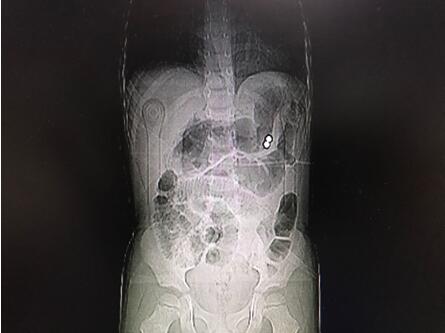

通訊員唐水平報道:近日,市中心醫(yī)院華新普外科收治了一位4歲的腹痛患兒,進院后檢查發(fā)現腹腔內有金屬異物及膈下游離氣體、腹腔積液,診斷為消化道穿孔并彌漫性腹膜炎。

經手術探查發(fā)現胃體近大彎側、曲式韌帶下方8cm處空腸及橫結腸系膜各有一0.5cm大小穿孔,在胃穿孔處的胃腔內外各發(fā)現一彩色磁力珠。經修補胃腸道穿孔及抗感染、補液治療,患兒術后順利康復院。